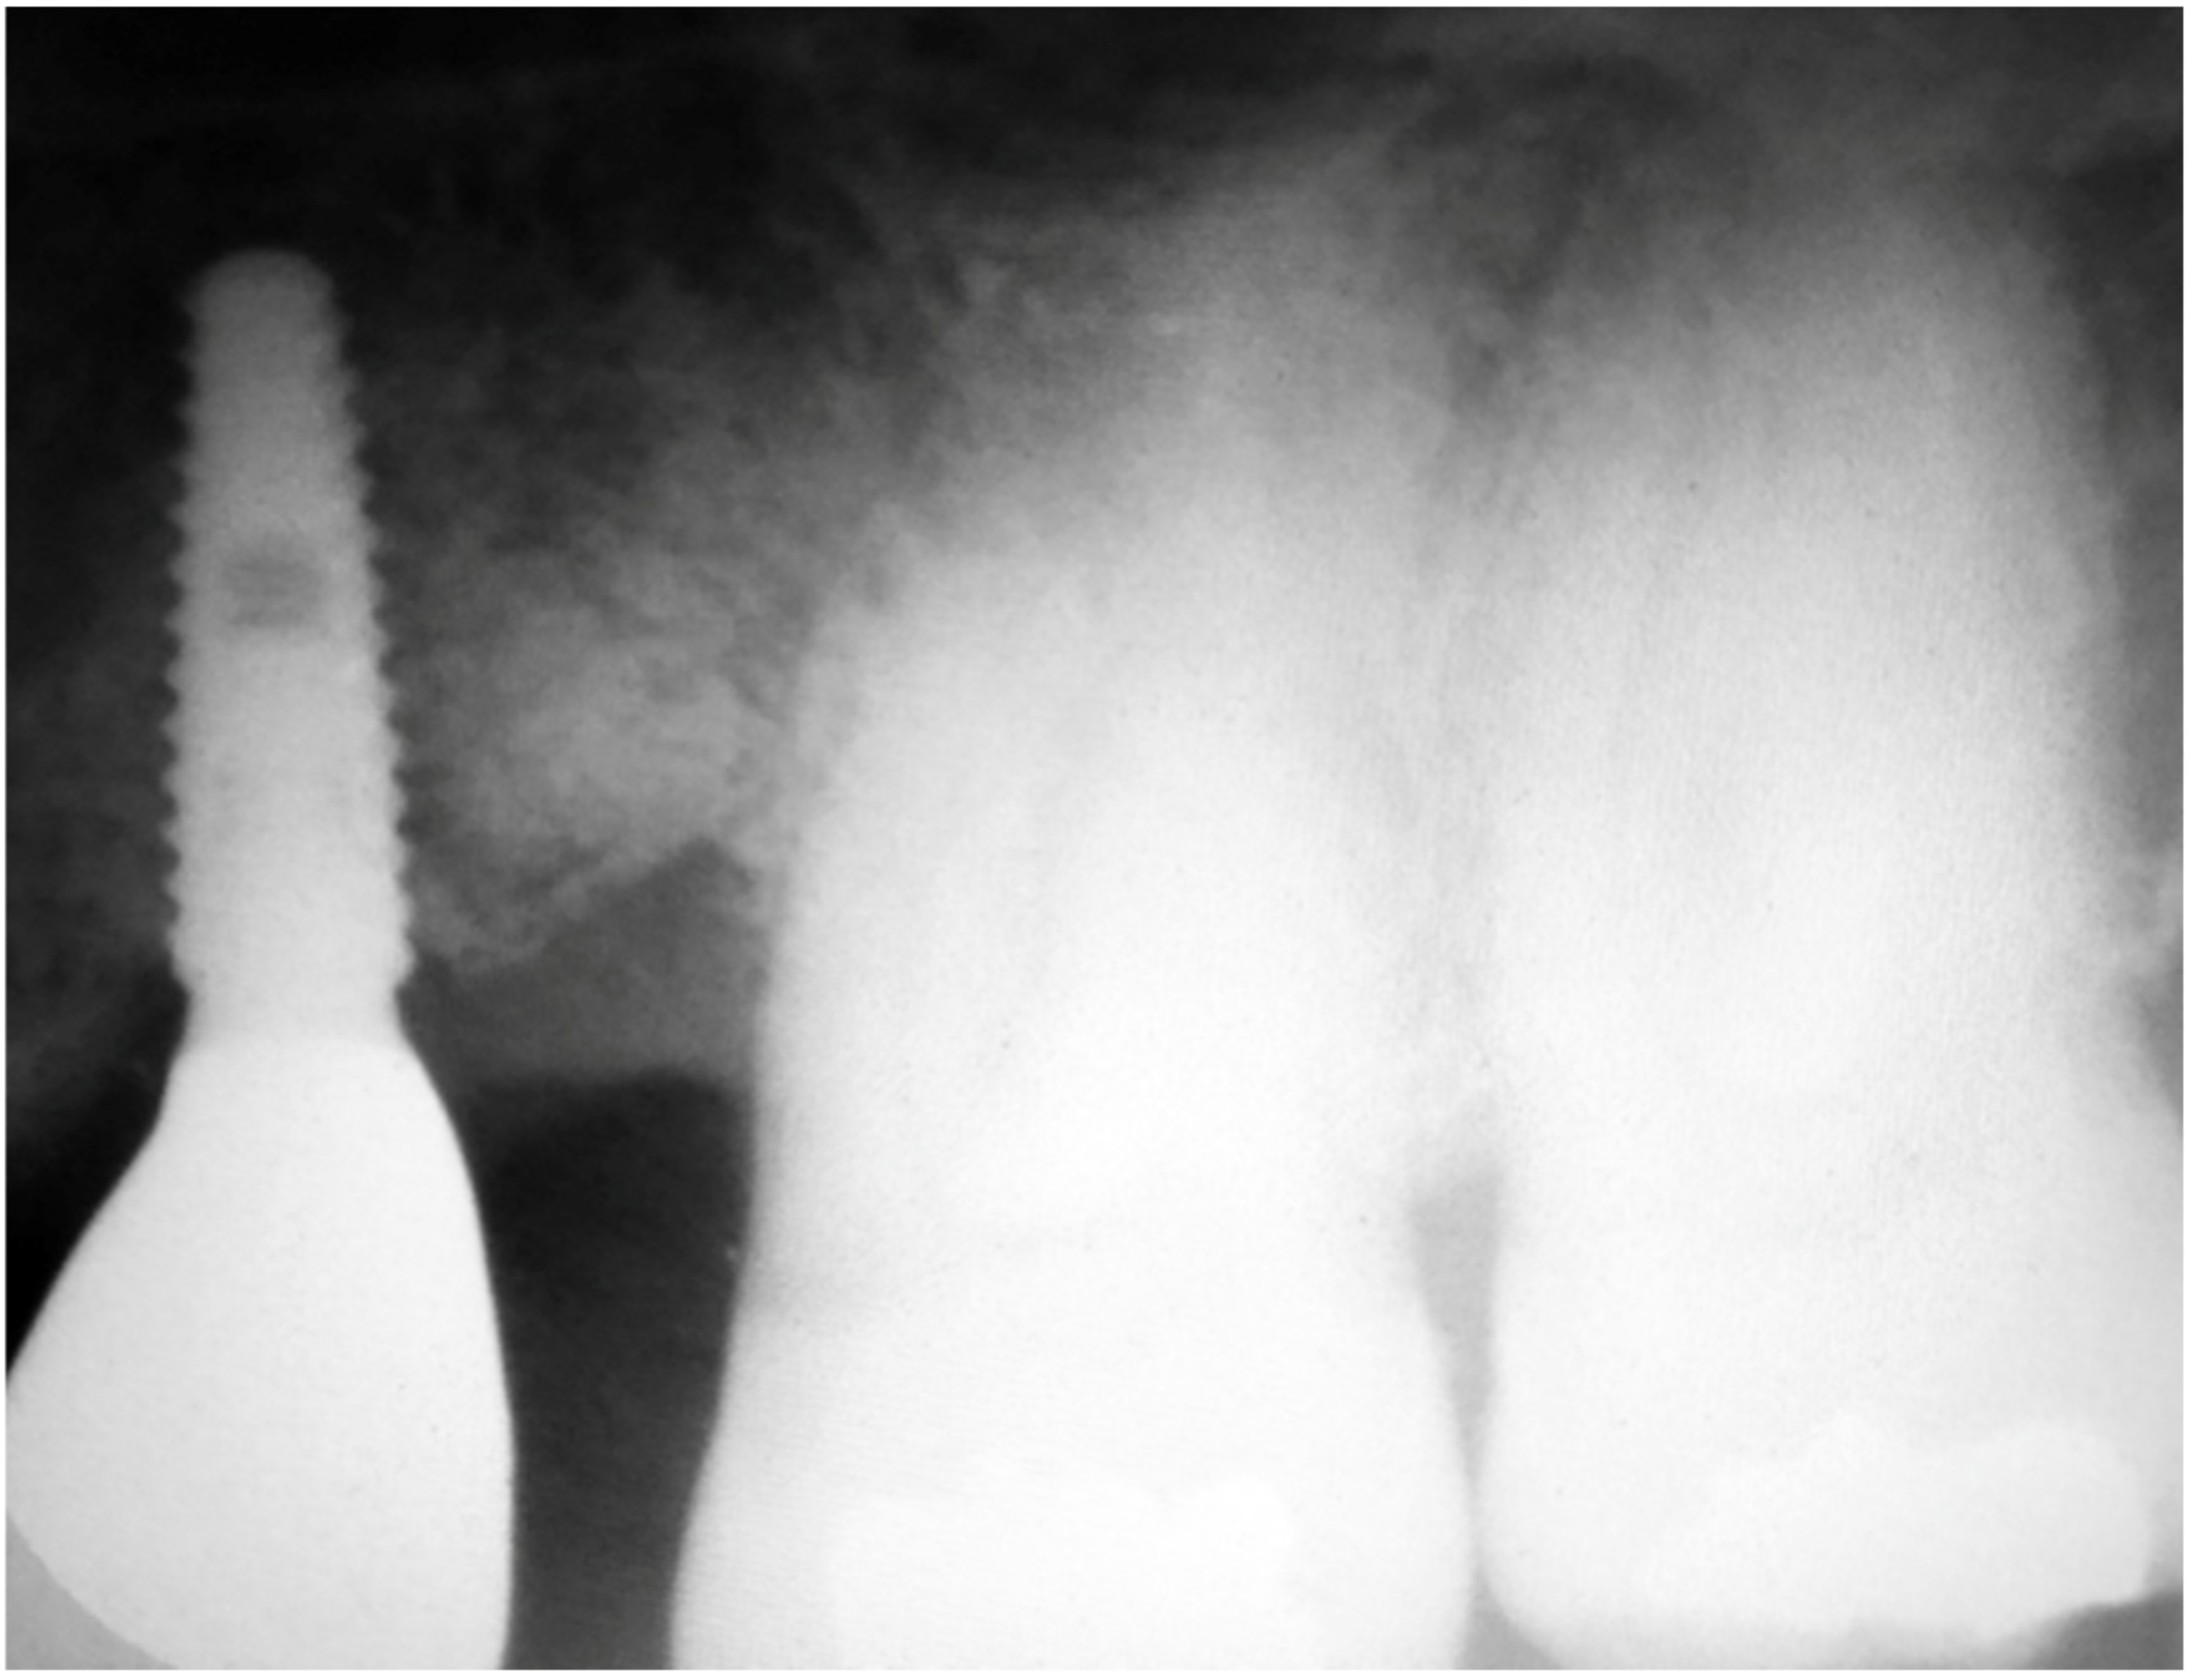

A 43-year-old male patient had a motorcycle accident and traumatically lost teeth 11 and 12. After a period of soft tissue healing the area was operated on in order to place two dental implants to replace the missing teeth (Figure 13 and Figure 14).

Figure 13.

The edentulous area showed some healing at the site of 12 but still a deep dehiscence on 11.

Figure 14.

Two implants in place of the one on 11 with several threads exposed.